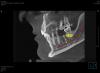

denis1987 Опубликовано 7 августа, 2013 Поделиться Опубликовано 7 августа, 2013 Вот такой вот пациент, планируется имплантация в области 46 зуба , снимки прилагаются. Вопрос в следующем, как лучше расположить имплант относительно антагониста, потому что не могу на КТ при позиционировании нормально попасть в плоскость с ним... Имплант планирую ставить 4.2 х 10, так как до НЧ канала 12.3 мм. Ссылка на комментарий

Zborzh Опубликовано 7 августа, 2013 Поделиться Опубликовано 7 августа, 2013 Старайтесь ориентировать ось на небные бугры антагониста. 1 1 Ссылка на комментарий

OMFS Опубликовано 7 августа, 2013 Поделиться Опубликовано 7 августа, 2013 Ставьте по оси на небные бугры, вестибулярно нкр (лучше аутокость) Ссылка на комментарий